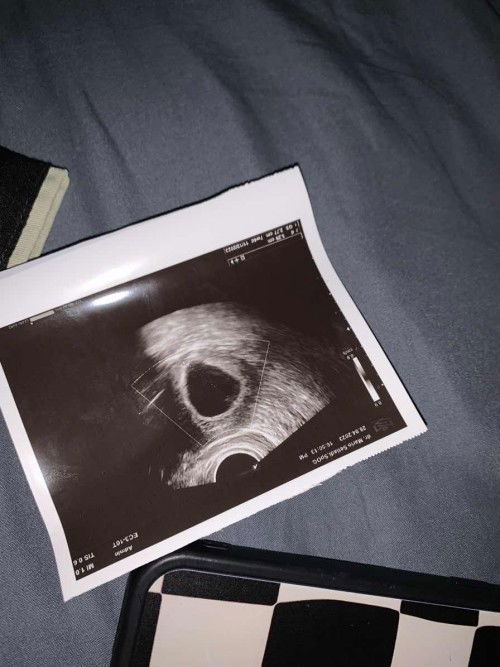

7 Week kehamilan

halo bun, aku hari terakhir haid nya tanggal 16 maret, kata dokter nya usia nya 7 weeks. tadi usg trasvaginal gaada janin nya, hanya ada kantong nya ukuran 2,77. dokter bilang ada kemungkinan hamil BO, katanya ditunggu 1 minggu lagi nanti dikasih tindakan kuret. Dokter juga bilang kalo mau kuret skrng juga gapap tapi aku bilang tunggu minggu depan aja, aku harus apa ya bun? aku bingung banget, aku dan suami Shock bgt 😥